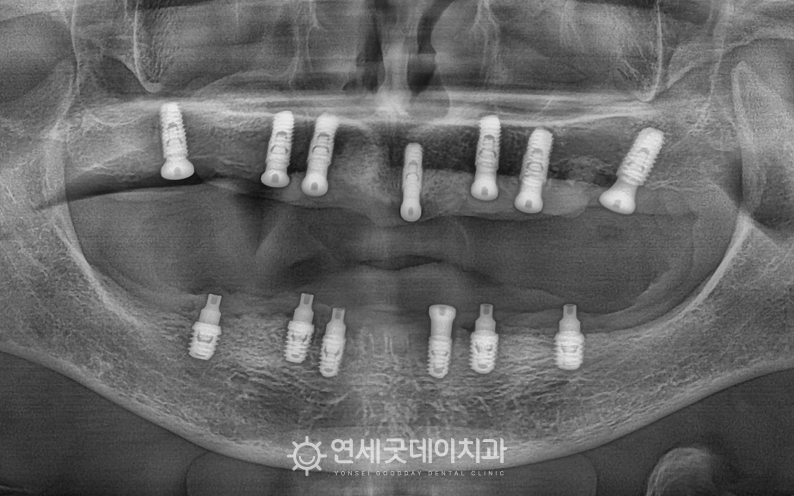

전체임플란트 및 상악동수술 치료전후 (50대)

환자분은 특히 상악 골소실이 심한 상태셨기 때문에 윗니의 잇몸뼈 두께가 얇은 상태에서 상악동수술 이후 오스템 임플란트를 식립해드렸으며

전체임플란트 치료를 마친 후 엑스레이 모습입니다. 꼭 필요한 위치에만 임플란트를 식립한 뒤